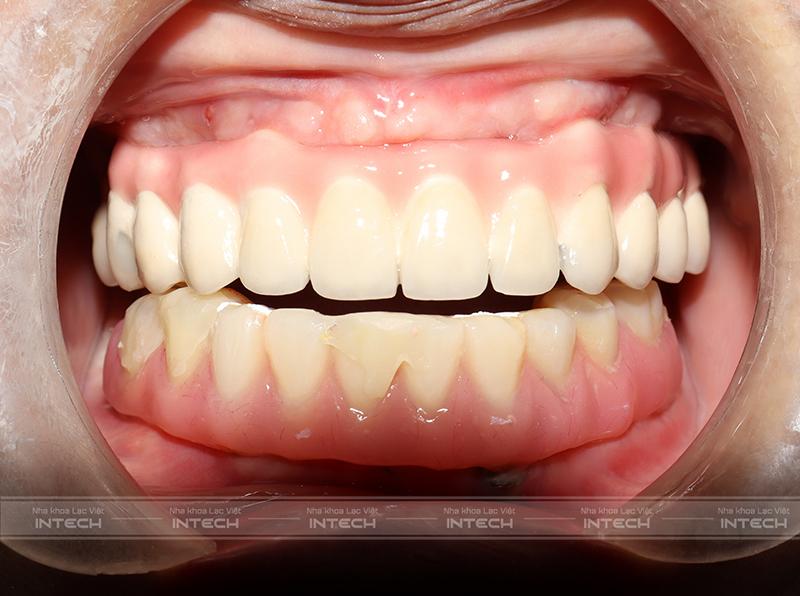

Như vậy, quá trình trồng răng Implant của cô Thủy đã hoàn thành. Công nghệ Safe Tech của Nha khoa Lạc Việt Intech đã hoàn toàn đáp ứng được những mong muốn về khôi phục khả năng ăn nhai và tính thẩm mỹ của khuôn mặt. Và từ nay, cô có thể sử dụng 2 hàm răng để ăn uống và cảm nhận giống như răng thật, chắc khỏe và bền vững theo năm tháng.

Dưới đây là hình ảnh trước và sau khi trồng răng Implant của cô Thủy:

Hình ảnh so sánh cô Thủy trước và sau khi trồng răng Implant tại Lạc Việt IntechHình ảnh so sánh cô Thủy trước và sau khi trồng răng Implant tại Lạc Việt Intech

“Sau khi lắp răng xong cô lên được vài cân. Ăn uống rất thích mà tư tưởng cũng thoải mái hơn nhiều. Cô làm xong hàm răng thì về cũng phấn khởi, nhà từ chồng đến con cái ai cũng khen.”

“Cô cảm thấy lắp hàm tạm khả năng ăn nhai đã cải thiện tới 70% rồi. Đến lúc lắp răng thật thì cô nghĩ cũng không khác gì răng thật của mình luôn. Ăn uống thoải mái mà không đau đớn hay ảnh hưởng gì cả”.